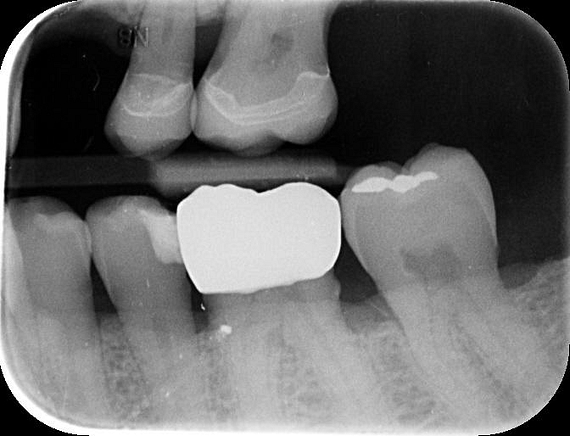

A radiographic assessment confirmed the proper integration and positioning of the implant.

At the final appointment, the crown was securely attached to the implant, resulting in a beautiful, natural-looking restoration.